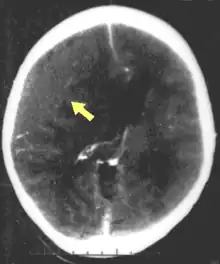

Hematomas, also focal lesions, are collections of blood in or around the brain that can result from hemorrhage.[11] Intracerebral hemorrhage, with bleeding in the brain tissue itself, is an intra-axial lesion. Extra-axial lesions include epidural hematoma, subdural hematoma, subarachnoid hemorrhage, and intraventricular hemorrhage.[38] Epidural hematoma involves bleeding into the area between the skull and the dura mater, the outermost of the three membranes surrounding the brain.[11] In subdural hematoma, bleeding occurs between the dura and the arachnoid mater.[23] Subarachnoid hemorrhage involves bleeding into the space between the arachnoid membrane and the pia mater.[23] Intraventricular hemorrhage occurs when there is bleeding in the ventricles.[38]